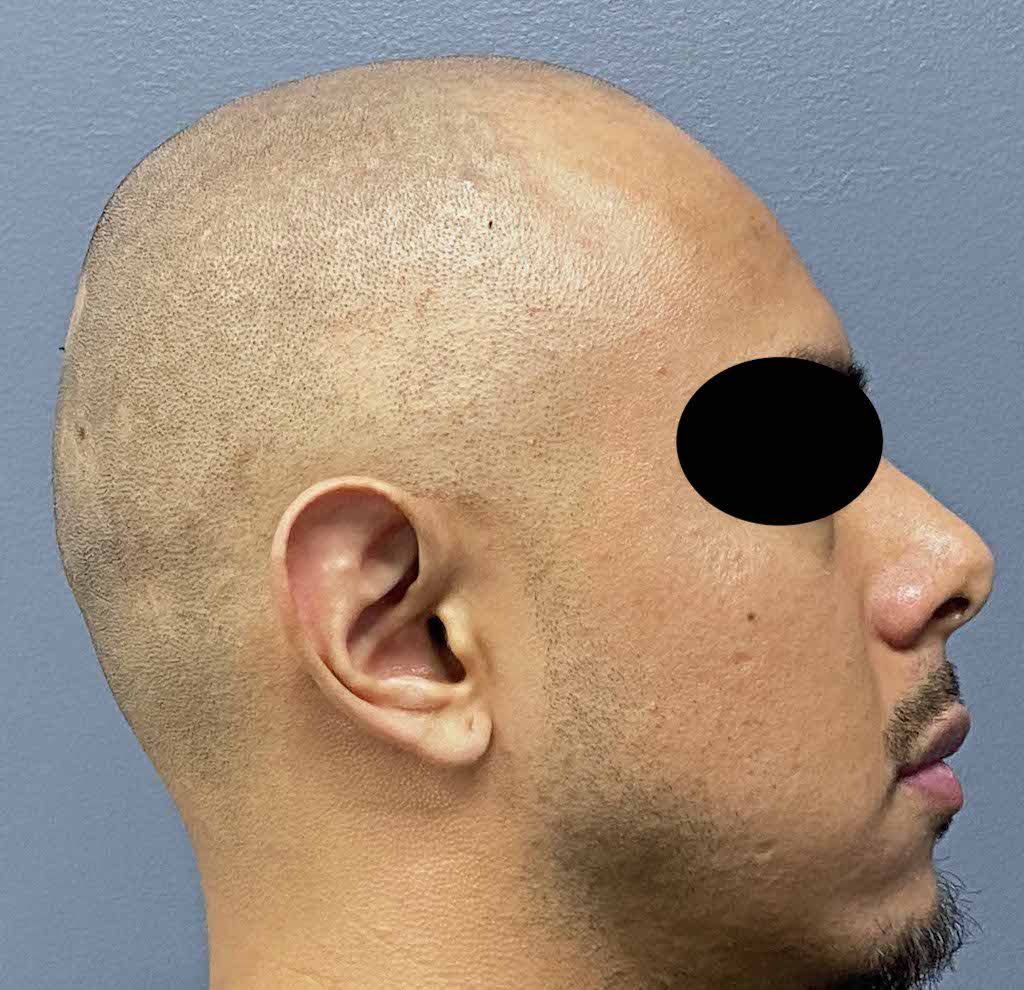

Patient 100

Desire for reshaping of an asymmetric flat back of the head in a shaved head male.

A combined back of the head reshaping procedure was done with a custom skull implant, sagittal ridge reduction and a right temporal muscle reduction.

Desire for reshaping of an asymmetric flat back of the head in a shaved head male.

A combined back of the head reshaping procedure was done with a custom skull implant, sagittal ridge reduction and a right temporal muscle reduction.